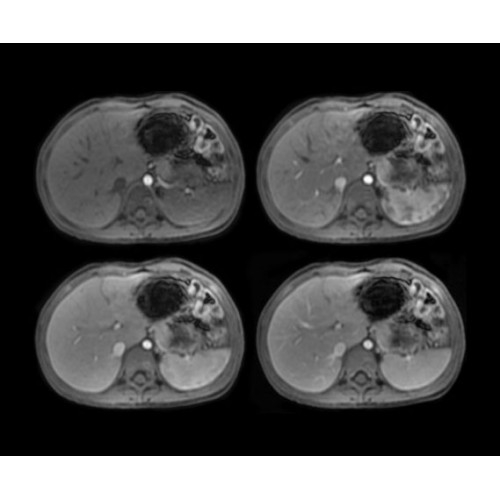

• BodyWorks — для визуализации абдоминальной и тазовой областей, подстраиваясь под запросы пользователя с учетом любых типов пациентов.

• OncoWorks — клинические приложения для обработки и визуализации анатомических и морфологических данных, специфичных для каждого типа онкологических образований.